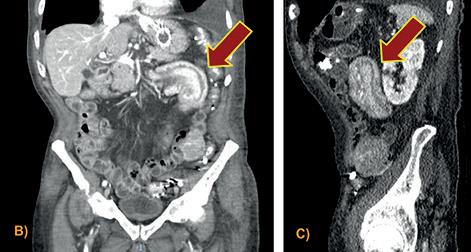

FIGURA 1: TOMOGRAFÍA DE ABDOMEN Y PELVIS CON CONTRASTE EV: En topografía pancreático-duodenal se observa una voluminosa tumoración de contornos lobulados con ligera heterogeneidad central, de 7,3 cm. podría corresponder a gran conglomerado adenopático. En el retroperitoneo y en el mesenterio, se observan múltiples ganglios con leve a moderado aumento de tamaño. En el hemiabdomen derecho se observa una tumoración voluminosa, asociada a una invaginación en topografía cecoascendente.

A)-B)Signo de donut o escarapela.C). Signo de la salchicha o psudoriñon. A); B) Signo de donut o escarapela. C). Signo de la salchicha o psudoriñon. D) Corte coronal. Servicio de Tomografía, Departamento de Imágenes, Hospital de Clínicas “Jose de San Martin” [Av. Córdoba 2351, CABA].